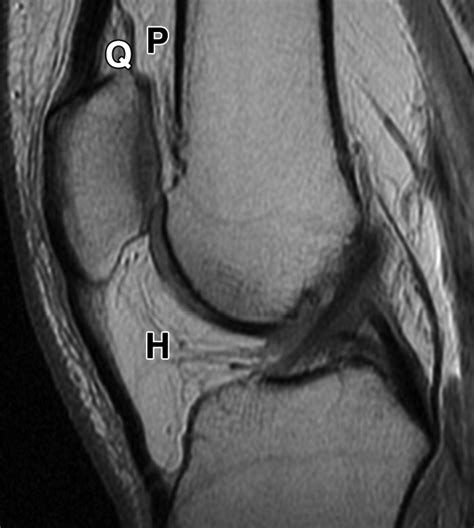

If you suspect you have Fat Pad Impingement, it is vital to seek a professional diagnosis. A physical therapist or orthopedist will typically perform a Hoffa’s Test. During this test, the practitioner will press their thumbs into the space below the kneecap while you fully extend your leg. If this triggers your signature pain, it is a strong indicator of the condition. In some cases, an MRI may be ordered to visualize the inflammation or to rule out other structural knee issues such as bursitis or tendinitis.